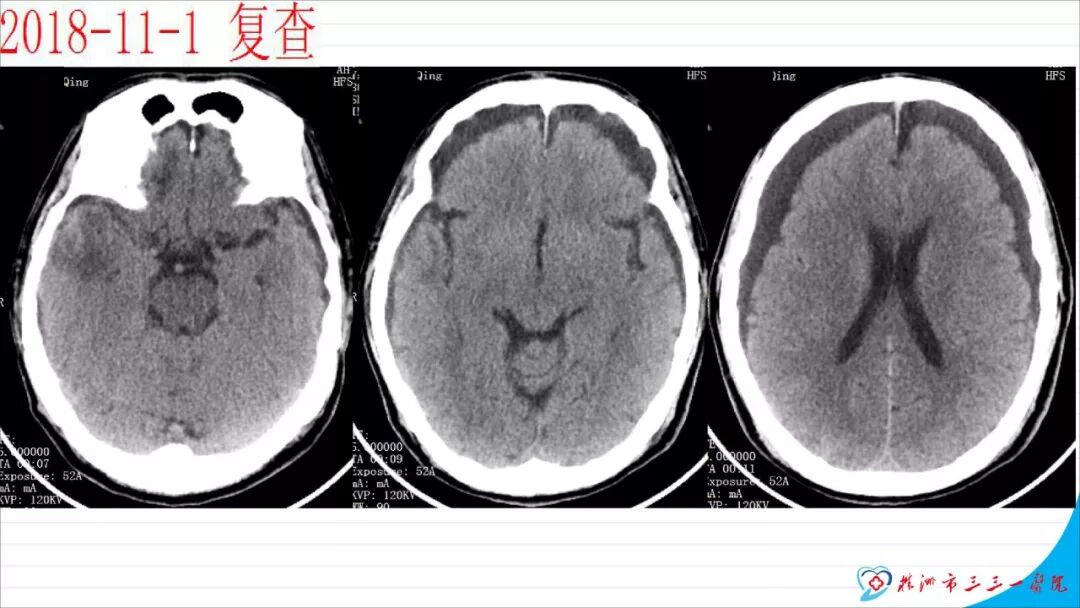

本文以“慢性硬膜下血肿自然演变一例”为题,恰当!因为此例患者系从急性硬膜下血肿自然演变而来。只是长期口服他汀没有起到预防作用。本例患者与其说是阿托伐他汀治疗慢性硬膜下血肿无效,还不如说是阿托伐他汀不能阻止急性硬膜下血肿向慢性硬膜下血肿演变的过程,当然,后续急性血肿变成慢性后,阿托伐他汀似乎也没有发挥治疗作用。需要指出的是,单药阿托伐他汀治疗急性硬膜下血肿并无成功病例报道,但是,本例报道还告诉我们,它还不能阻止急性硬膜下血肿向慢性血肿演变,值得关注。 谈到阿托伐他汀治疗慢性硬膜下血肿,我们是始创者。为此,看到作者似乎有点抱怨的情绪,我得做些解释。我们ATOCH试验,验证的是阿托伐他汀治疗慢性硬膜下血肿比安慰剂能更有效促进血肿吸收,没有发现也没有努力去验证阿托伐他汀治疗慢性硬膜下血肿100%有效,因此发生治疗无效很正常。 保守治疗的始作俑者是英国人,他们1962年就提出地塞米松治疗慢性硬膜下血肿。但是,迄今为止,无论是英国人提出的地塞米松、美国人提出的氨甲环酸或血管紧张素转换酶抑制剂,还是德国人提出的塞來西布,日本人提出的汉药,国内许多单位自行研究提出的血府逐瘀丸,作者单位的“传统”方法红花注射液治疗慢性硬膜下血肿都没有经历严格随机双盲安慰剂对照研究,也从未被大宗病例报道证实过有效。由于未被RCT(随机对照临床试验)证实过,加上一部分慢性硬膜下血肿不必治疗也可以自我吸收(这在我们ATOCH里的安慰剂组中已经观察到,但我们发表论著时没有刻意提出这一点而已),除他汀疗法之外的药物疗法被怀疑是否真具有疗效就顺理成章了。这也是我们的阿托伐他汀治疗慢性硬膜下血肿在保守治疗药物队伍中“一骑绝尘”的理由。后续西南医科大学和香港中文大学还均报道使用阿托伐他汀可以预防慢性硬膜下血肿术后复发。而且,除了有RCT结果支撑其有效性外,安全性明显优于上述各个西药又不像中药或汉药那么含糊,也使得阿托伐他汀成为目前保守治疗慢性硬膜下血肿应用最多的药物。 但毫无疑问,实践中确实屡屡有发现效果不佳的病例。为什么会这样呢?可能有2个理由: 1、确实存在一部分对他汀治疗反应不佳的患者。我们的ATOCH中,阿托伐他汀试验组就有11例患者因无效转去接受手术(对照组则多达23例); 2、ATOCH试验长达8周,有些患者家属和医生都没有耐心等待8周。也就是说,没有等到药物作用显现就转保守治疗为手术治疗。在同样状况下,即使作为发明者,我也不敢“阻扰”患者转手术治疗,因为这意味着风险转嫁。而这种“保守治疗未到时间”(这样提可能不严谨,因为没有规定时间,只有经验时间)就转手术治疗,会增加阿托伐他汀治疗慢性硬膜下血肿的“无效率”。 有鉴于此,我们团队在张建宁教授指导下,从2014年就开始优化阿托伐他汀疗法,本人以此优化的独门方法就治愈了多达200余例各种慢性硬膜下血肿患者。最近,有上海同行私下告诉我,他用类似我的优化方法保守治疗慢性硬膜下血肿多例,还没有失败过。我跟他开玩笑:“那是你治疗的病例还不够多。”实际这不是开玩笑,因为本人有失败经验。目前,我们团队正积极推进ATOCHII试验,就是要证明我们的优化疗法更加有效,期待奉献给世界一个更加好用的治疗慢性硬膜下血肿新方法。 最后需要特别指出的是,慢性硬膜下血肿与急性硬膜下血肿和亚急性硬膜下血肿并非一定有如父如子的“传承”关系。实践中,绝大多数患者都没有急性硬膜下血肿过程,尤其是老年患者第一次查影像学多数就可以确诊慢性硬膜下血肿了,患者之前并没有经历急性硬膜下血肿这种剧烈损伤过程。还有,脑转移癌可以发生类似慢性硬膜下血肿的血肿性病变,先天性蛛网膜囊肿、脑池囊肿术后常见并发症就包括硬膜下血肿。笔者诊疗慢性硬膜下血肿接近300多例,还见过教科书和个案报道没有记载的各种非脑外伤相关慢性硬膜下血肿的病例。相比于脑外伤引起的急性和亚急性硬膜下血肿,慢性硬膜下血肿是处理简单且病情稍显轻微的疾病,但其发生机制却远比急性和亚急性硬膜下血肿更为复杂,值得进一步深入研究。 江荣才 教授 副主任兼NICU主任 天津医科大学总医院神经外科![]()